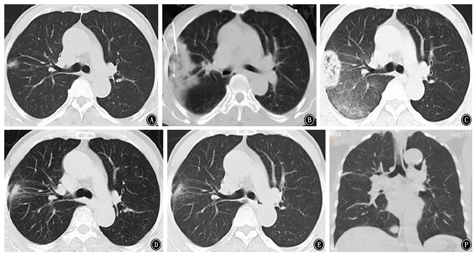

值得注意的是,由于GGN非手术活检诊断率低、出血风险高等特点,消融同步活检在高度可疑恶性GGN病灶中的应用正备受关注[26]。但目前更多的关注点在于消融是否对病理结果造成影响以及同步操作的技术可行性,而对于消融远期疗效的报道相对较少。本中心也开展了这项技术,现有的结果显示消融同步活检可获得不亚于单独穿刺的病理诊断率,且病灶控制良好,典型病例见图3。